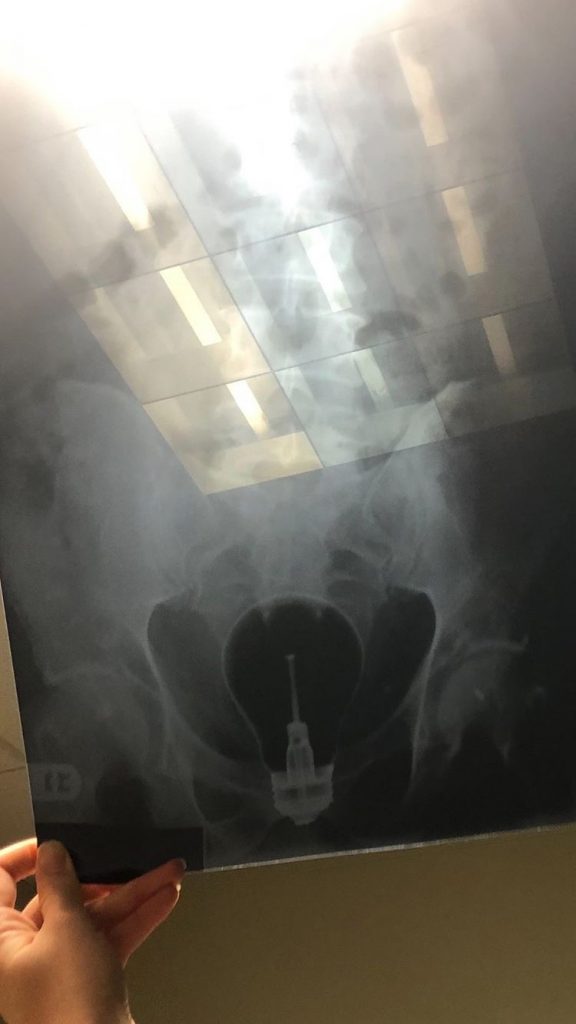

Rectal Foreign Body Gallery Rectal Foreign Body By Nicole Angemi|2024-09-16T12:09:23-04:00January 19th, 2020|Foreign Bodies, The Gross Room, FREAK ACCIDENT| Read More 19

Cock Ring Comp Gallery Cock Ring Comp By Nicole Angemi|2024-09-16T12:11:56-04:00January 18th, 2020|The Gross Room, FREAK ACCIDENT, Foreign Bodies| Read More 39

Ass Ault Gallery Ass Ault By Nicole Angemi|2025-04-04T14:02:29-04:00January 9th, 2020|The Gross Room, MEDICAL, Foreign Bodies, Assault| Read More 19

RFB Gallery RFB By Nicole Angemi|2024-09-16T12:22:38-04:00January 8th, 2020|Foreign Bodies, The Gross Room, FREAK ACCIDENT| Read More 25